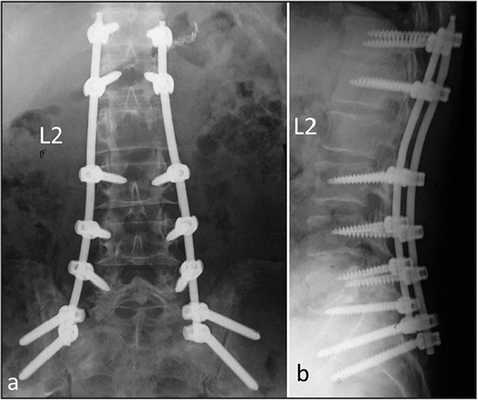

Стабилизация поясничного отдела.

Коррекция кифоза грудного отдела.

3 месяца после операции.

Нестабильность позвоночника считается одним из распространенных заболеваний и основным методом лечения является транспедикулярная фиксация подвижного сегмента, декомпрессивная ляминэктомия, дискэктомия с установкой между телами позвонков кейджа который фиксирует сегмент на 360 градусов (золотой стандарт). В подобных ситуациях метод обеспечивает надежный спондилодез у 80- 95% пациентов. ТПФ является одним из наиболее часто применяемых методов оперативного лечения заболеваний и травм в связи с тем, что современные хирурги стараются добиться спондилодеза на 360°. Достичь этого позволяет сочетание ТПФ с межтеловым спондилодезом, что обеспечивает высокую частоту костных сращений и отсутствие остаточной незначительной подвижности в передних отделах прооперированного сегмента. Поэтому при успешном завершении операции и правильном восстановлении пациенты гарантировано избавляются от болевого синдрома.

При правильном проведении техника обеспечивает ярко-выраженные положительные результаты лечения в подавляющем большинстве ситуаций. С ее помощью возможно частичное или даже абсолютное восстановление функциональной способности позвоночника после перенесения серьезных травм, приведших к параличу. Она же позволяет устранить болевой синдром, сопровождающий заболевания, включая сколиоз.